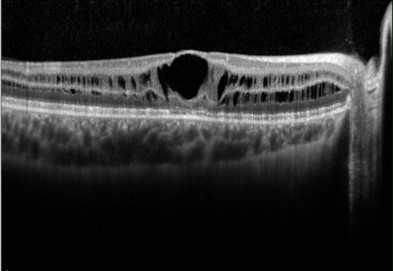

The characteristic sign of X-linked retinoschisis is a spoke-wheel appearance radiating from the fovea with OCT showing splitting of the neurosensory retina at multiple retinal layers creating schisis cavities. Peripheral retinoschisis is reported in 50-70% of the cases and can lead to complications such as retinal detachment and vitreous haemorrhage.

More infoSpectralis OCT macular line scans (right and left eye)